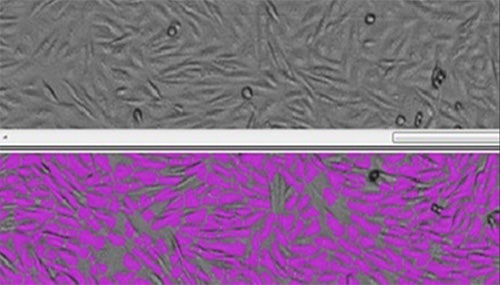

- Integrated, validated systems can help reduce audit‑trail gaps and improve consistency in cell‑based potency assays.

The article highlights how non‑validated instruments, manual workflow handoffs, and variable image‑analysis algorithms can introduce risk by compromising traceability and reproducibility. Bolus emphasizes the importance of selecting imaging solutions designed for regulated environments, integrating workflows to minimize data transfer points, and approaching validation as both a technical and business decision as QC labs prepare for increased automation and AI adoption.